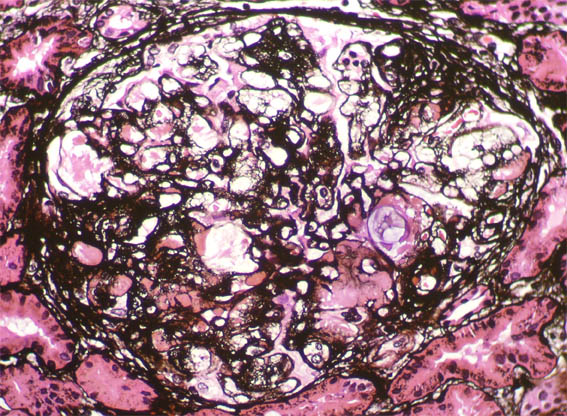

A male patient, 32 years old, was referred for renal biopsy because of a 2 year history of progressive proteinuria until full nephrotic syndrome, without impaired renal function.

Laboratory: normal blood count, creatinine 1.1 mg/dL, BUN 19 mg/dL. Proteinuria 7.3 g/24h with no casts or hematuria. Tests negative for viruses and autoimmunity. Normal complement. Negative cryoglobulins.

Figure 7. Methenamine-silver stain, X400.

Figure 8. Methenamine-silver stain, X400.

Figure 9. Methenamine-silver stain, X400.